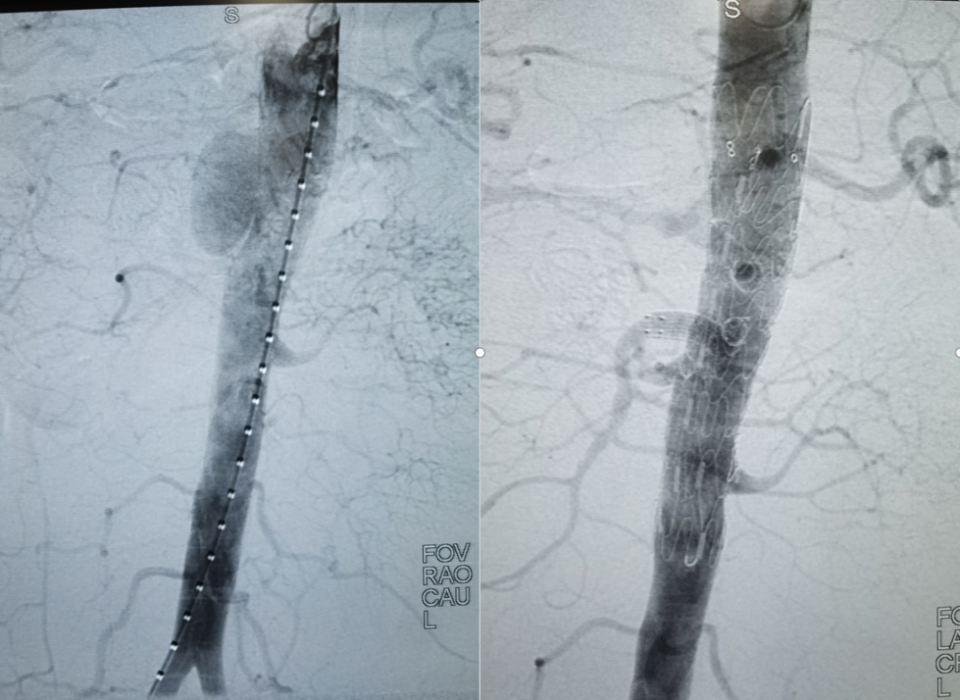

一系列精准操作完成后,造影显示腹主动脉支架及四个内脏动脉支架血流通畅无内漏,实现了动脉瘤完全隔绝,所有分支完整保留。术后王先生即清醒,无任何并发症。

术前术后造影对比